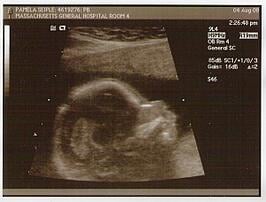

Anyway, I'm also happy to report that (as far as they can tell via ultrasound) Baby Lump is completely happy and healthy (okay - I added the happy part). James and I could see all of the bones (fingers, toes, spine, ribs, etc.) as well as the eyes, kidneys, brain, stomach and

I asked the technician how big the baby is at this point, but he said it's tough to tell since he/she is confined to the womb and can't exactly stretch out straight. However, all the week-by-week pregnancy sites I visit tell me the baby is approximately five inches long - "about the size of the baked potato." It's funny how many of these sites use food - often fruit - as a means of measurement. I swear, a few weeks ago the baby was the size of a peach.

Check out the "Sonograms" page for more baby pictures!

Oven Timer: 17 weeks, 2 days